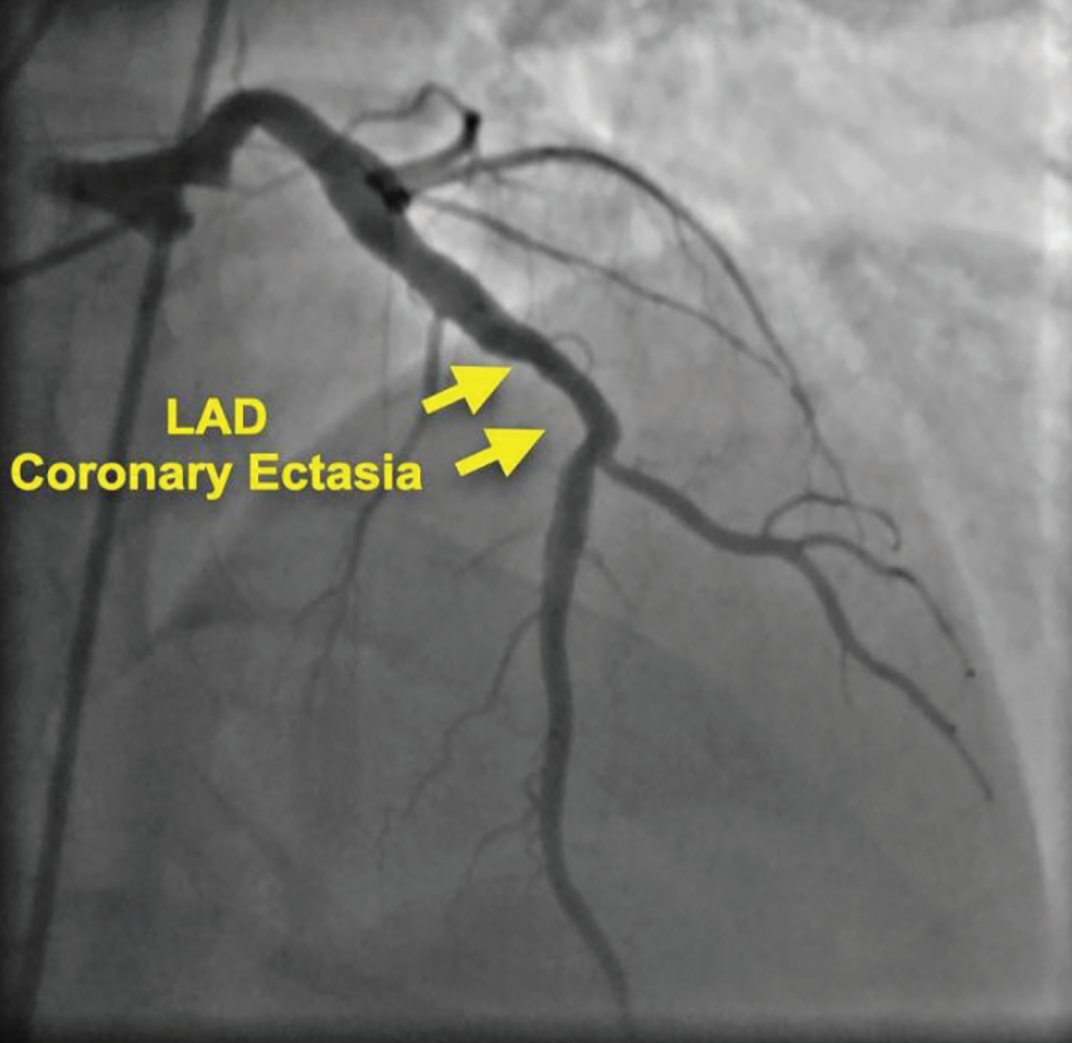

一名53岁男性患者,有吸烟史,但无其他CAD危险因素,因胸痛就诊。患者被诊断为非ST段抬高型心肌梗死(non-ST-elevation Myocardial Infarction,NSTEMI)。超声心动图显示前壁轻度运动减弱,射血分数为50%。次日早晨,冠脉造影显示LAD扩张,且在对角支主要分叉处存在大量血栓,但前向血流存在,TIMI血流分级为3级(图3)。

图3:病例2的初始造影:可见血栓存在的LAD扩张